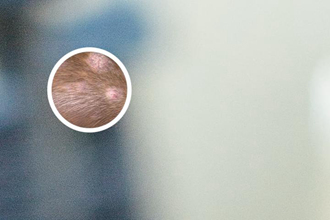

308激光,又稱準(zhǔn)分子激光,是一種科學(xué)的光療技術(shù),廣泛用于治療白癜風(fēng)。其原理是利用308nm波長的激光照射白斑患處,刺激黑素細胞活性,促進黑色素生成,從而恢復(fù)皮膚顏色。

鄭州308激光對白斑的治療的效果因個體差異而有所不同,但臨床數(shù)據(jù)顯示,有效率多達較高以上。療程通常為10次以上,每周照光1-2次,每次2-3分鐘。多數(shù)患者在一個療程后可見到顯然改善,1-3個月左右可恢復(fù)正常膚色。